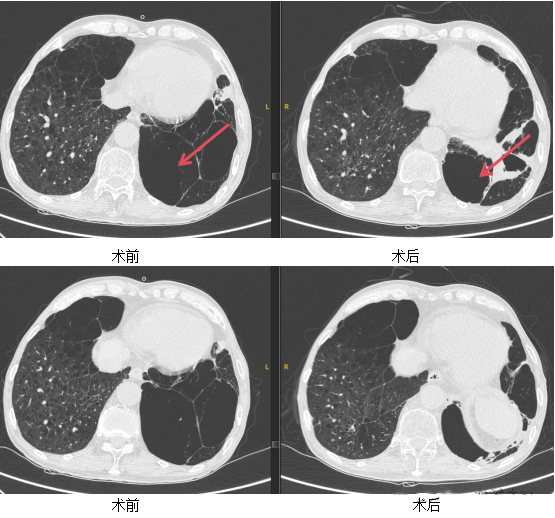

CT术前、术后对比:肺大疱明显缩小。